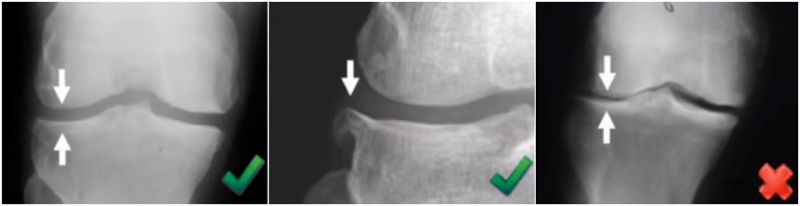

屈曲20°外翻应力:看外侧软骨

外翻应力片可以辅助评价外侧间室关节软骨厚度是否正常,以及内侧副韧带功能是否完整。外侧全层软骨、外侧有骨赘的情况下都不是禁忌证,如外侧出现软骨磨损则为禁忌证。

外翻应力片还可以观察内侧间隙,如内侧副韧带出现挛缩,间隙狭窄,那么此时不适合单髁。

检查时注意X线的投照角度要平行于关节线方向,以保证准确。

可以矫正畸形,恢复关节间隙和MCL张力